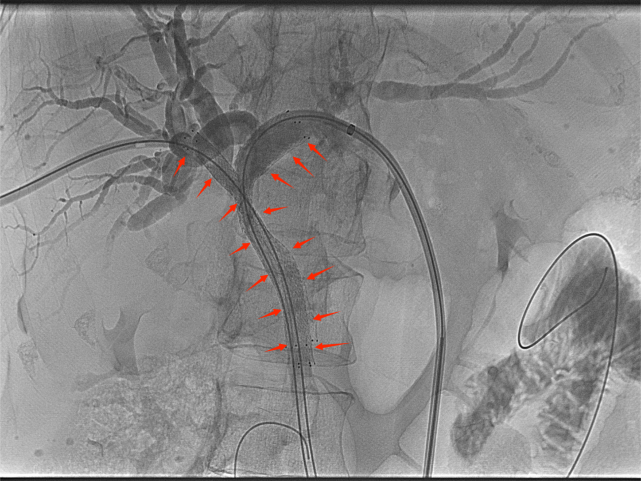

高位胆道梗阻支架置入

胆道支架置入能很好地弥补经皮肝穿刺胆道引流术的不足之处,通过在胆管狭窄/阻塞处安置金属支架,解除胆道梗阻、恢复通畅,促进胆汁入肠,改善消化功能的同时无需长期带管,显著提高了生活质量,适合短期内有效解除胆道梗阻的患者(如恶性胆道梗阻)。